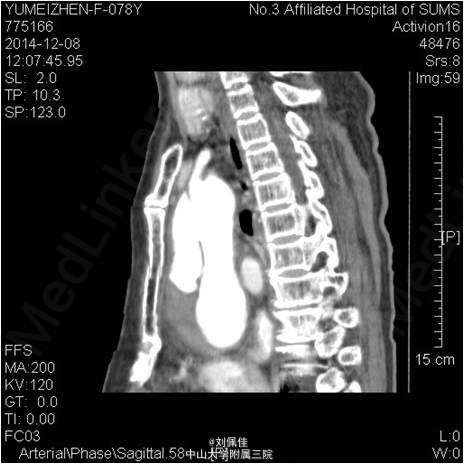

入院后多次复查心梗三项均为阴性。心电图与入院相较变化不大。入院:WBC 13x10e9/L,HGB 85g(小细胞低色素),ESR:45.00mm/H;CRP:153.200mg/L;白蛋白28.800g/L。CA125 90U/ml。转氨酶、BUN、Cr正常。血清LDH 285U/L。 床旁心脏彩提示:心包积液。予以心包穿刺抽液。 患者活动后胸闷、气促由心包积液所引起,暂不考虑急性冠脉综合征,停用抗血小板、抗凝药物。予可乐必妥抗感染、护胃、营养心肌、通便、镇静安眠、心包引流等治疗。 2014-12-8日行胸部CT提示:主动脉夹层(Debakey II型),并血栓形成。请介入科会诊,介入科医师会诊,建议转至外院心胸外科行手术治疗Stanford A型主动脉夹层。与患者家属沟通后,患者签字拒绝手术,表示愿意接受内科保守治疗。 予加用康忻5mgQd控制心率在60-70bpm,硝普钠控制血压在100/60mmHg左右。根据患者血压、心率情况,逐渐调整药物,现予康忻5mgBid,蒙诺5mgQd治疗,血压波动在95-115/55-65mmHg,HR 75-90bpm。 患者入院后偶有心前区、季肋部刺痛,阵发性,考虑与心包摩擦相关。未诉腹痛、背痛,未出现明显撕裂样疼痛。住院期间病情尚平稳,未发现夹层进一步撕裂的临床表现。